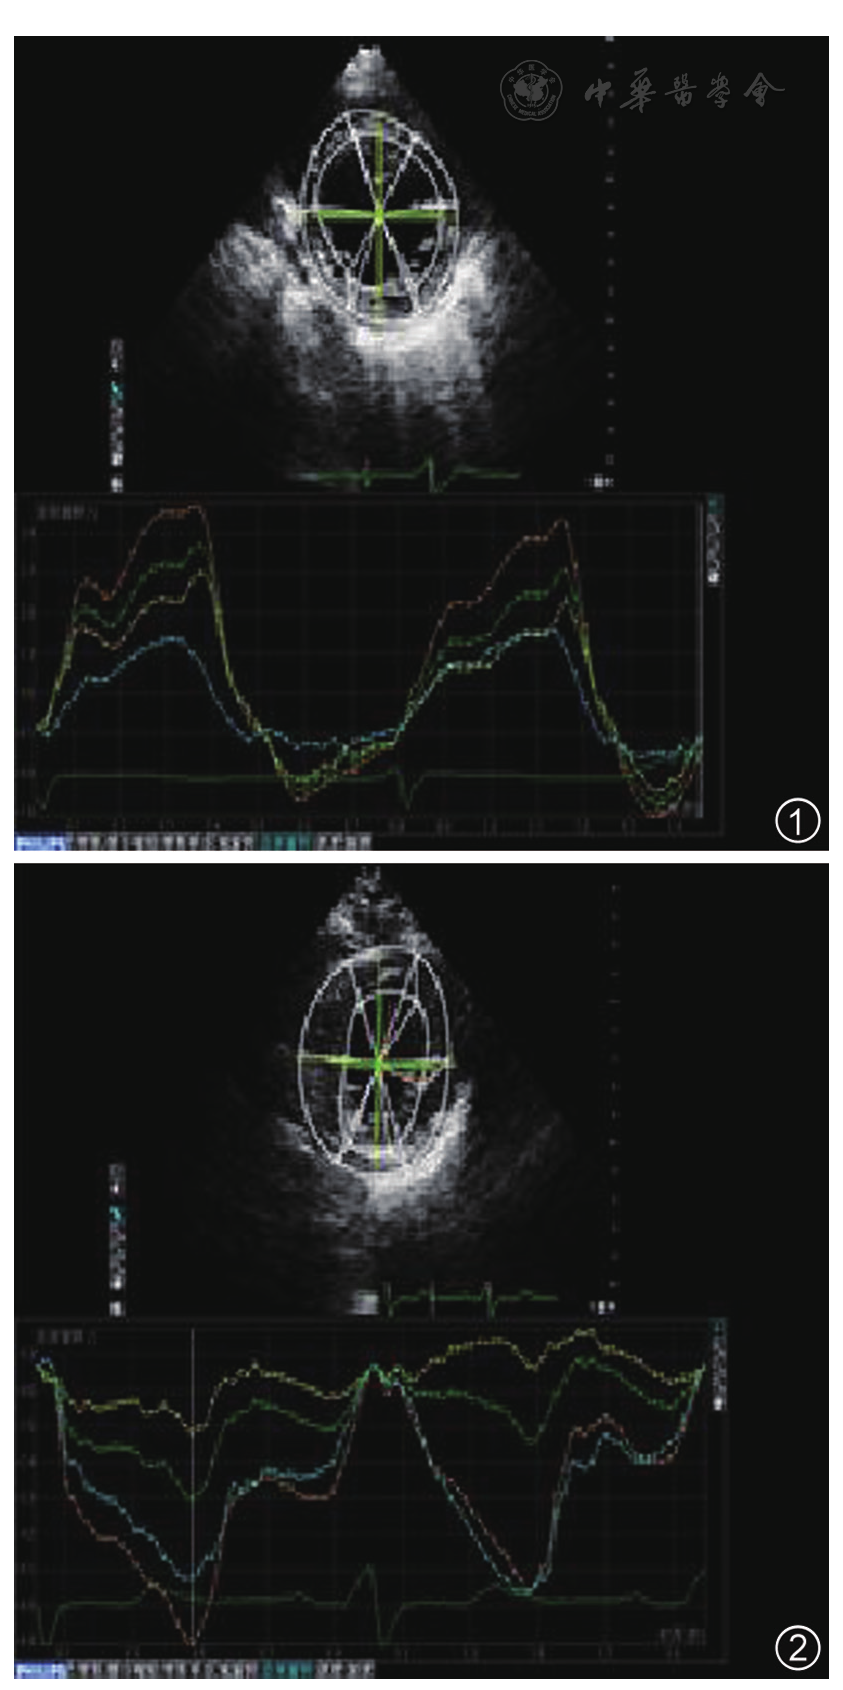

图2 扩张型心肌病2组患者即心尖顺时针旋转扩张型心肌病患者左心室心尖水平旋转角度曲线图。4条曲线为顺时针旋转,收缩期呈逆向单峰曲线